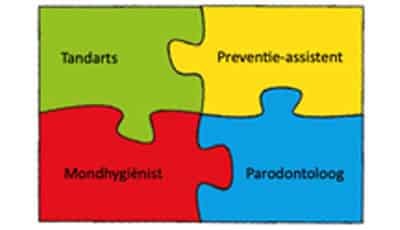

Voorlichting

Het geven van voorlichting is het domein van de mondhygiëniste, preventie-assistente en tandarts (-parodontoloog). Het is belangrijk om met de patiënt te bespreken wat ontstoken tandvlees is, hoe het ontstaat, wat de risicofactoren en effecten zijn en wat de vervolgstap is. Met behulp van de beschikbare folders en kaarten is het makkelijk aan de patiënt uit te leggen. Na de voorlichting kan samen met de patiënt het zorgdoel worden bepaald.